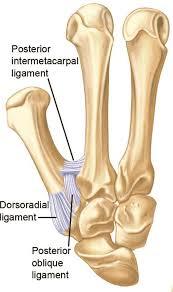

Significance of dorsal radial CMC ligament?

Dorsal trapezium to dorsal MC base. Strongest ligament. Torn in dorsal dx.